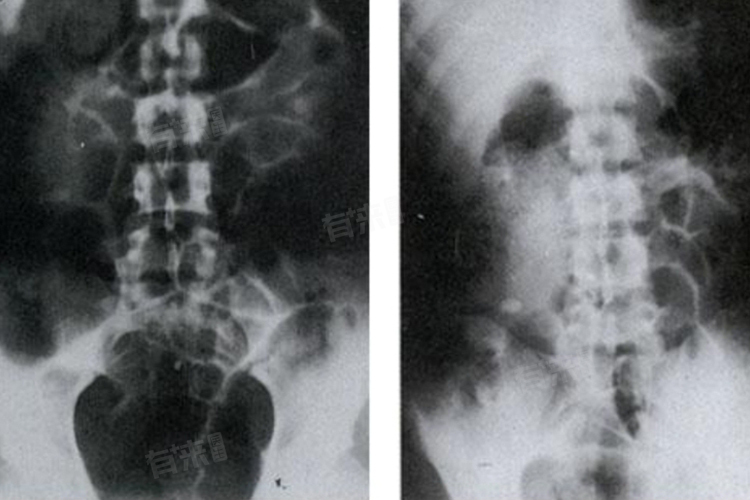

- 阑尾粪石:部分患者可在阑尾管腔内看到高密度影,即阑尾粪石,其发生率约为43%-65%,与急性阑尾炎有密切关系,且易引起阑尾坏死穿孔。